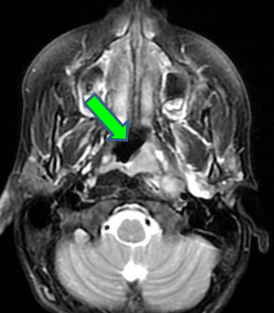

- Site de prédilectiond des carcinomes épidermoïdes naso-pharyngés